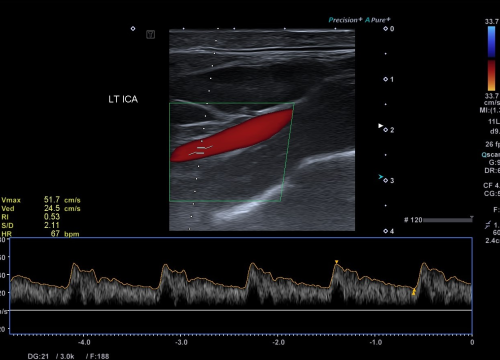

Svjetski dan zdravlja: Ateroskleroza svjetski ubojica broj jedan

Povodom svjetskog dana zdravlja o aterosklerozi kao najvećim javnozdravstvenim problemom i vodećim uzrokom bolesti i smrti na svijetu, pričali smo s doktorom specijalistom neurologije dr.